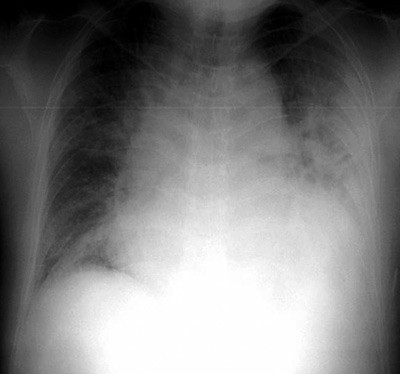

Blodprøver ved innkomst viste en normocytær og normokrom anemi (Hb 10,9 g/100 ml (13,4 – 17,0)), redusert antall hvite blodceller og blodplater (LPK 3,4 g/l (3,5 – 10,0), TPK 94 g/l (145 – 390)), samt lett nyresvikt (kreatinin 125 µmol/l (60 – 105), urinstoff 13,4 mmol/l (3,5 – 8,1)). Det var normale verdier av elektrolytter (natrium 142 mmol/l (137 – 145), kalium 4,7 mmol/l (3,6 – 5,0)), blodsukker (4,0 mmol/l (4,0 – 6,3)), hjerteinfarktmarkører og infeksjonsprøver, men høye lipidverdier (totalkolesterol 10,8 mmol/l (3,9 – 7,8) og LDL-kolesterol 7,8 mmol/l (2,1 – 4,9)). Ved røntgen thorax fant man et betydelig forstørret hjerte og moderat lungestuvning (fig 2). Det var normale funn ved CT-undersøkelse uten kontrast av hjernen. Ekkokardiografisk undersøkelse viste en dilatert, tynnvegget venstre ventrikkel (endediastolisk diameter 7,0 cm) med uttalt generell hypokinesi (ejeksjonsfraksjon 20 %), samt en liten mengde perikardvæske. Ingen klaffepatologiske forhold ble påvist og høyre hjertehalvdel var normalt stor.